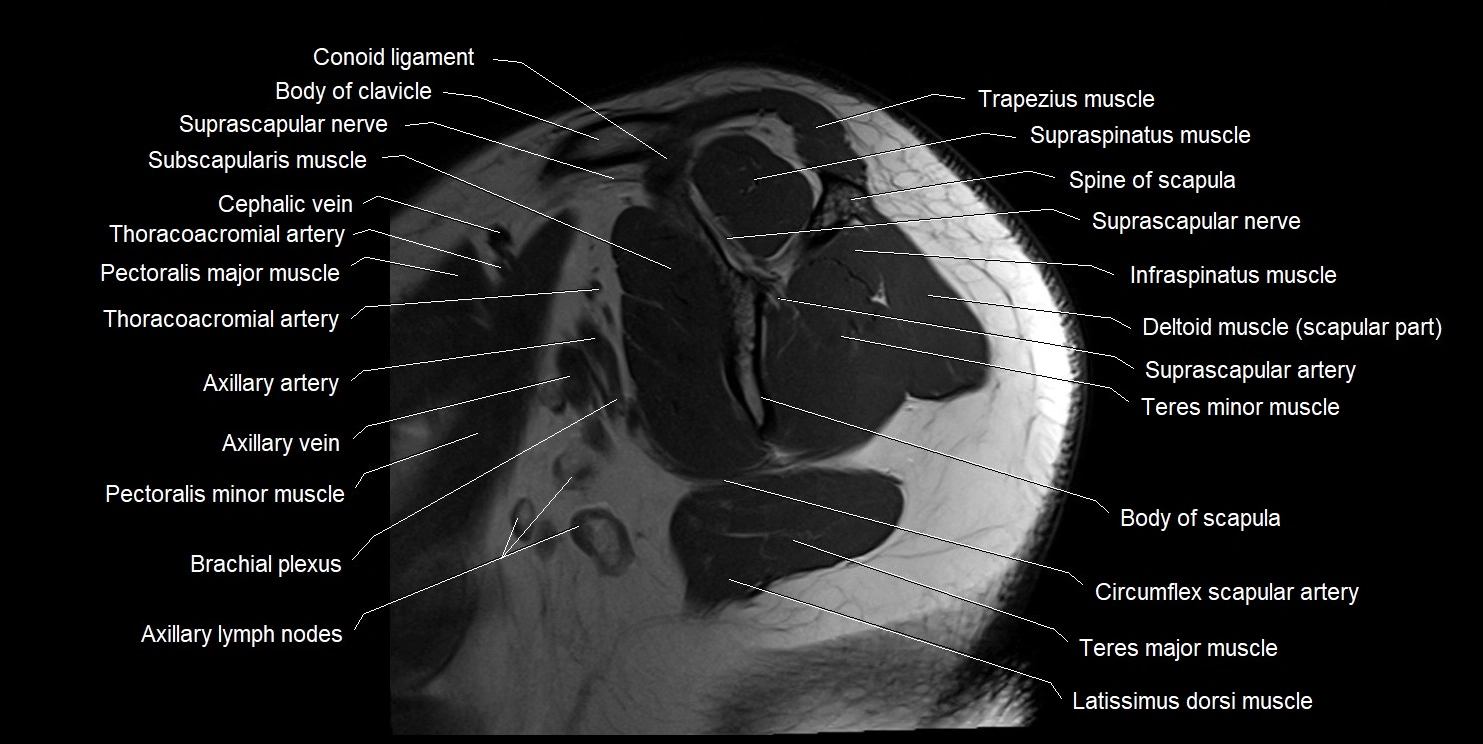

CT image

image